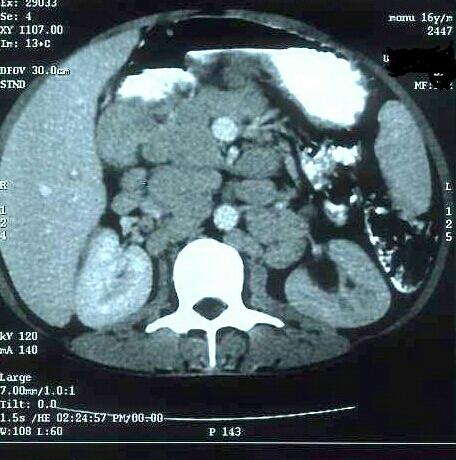

Sinus histiocytosis with massive lymphadenopathy (SHML) is a rare and benign cause of lymphadenopathy and was first described in 1969. This disease commonly presents in children and young adults with supra-diaphragmatic lymphadenopathy mainly at cervical nodal sites, composed of a population of histiocytes. Since its description, over 400 cases have been described, but there are few reports in the literature on its association with lymphomas. This case report describes a case with co-existing SHML and anaplastic large cell lymphoma (ALCL). The diagnosis of SHML in our patient did not alter the clinical outcome and the patient responded well to treatment for ALCL. Clinicians should maintain a high index of suspicion in cases of infra-diaphragmatic SHML for the presence of occult lymphoma.

伴巨大淋巴结病的窦性组织细胞增生症(SHML)是一种罕见的淋巴结病良性病因,于1969年首次被描述。该病常见于儿童和青年,主要表现为膈上淋巴结病,以颈部淋巴结部位为主,由一群组织细胞组成。自其被描述以来,已报道了400多例,但关于其与淋巴瘤关联的文献报道较少。本病例报告描述了1例同时存在SHML和间变性大细胞淋巴瘤(ALCL)的病例。我们患者的SHML诊断并未改变临床结局,且患者对ALCL治疗反应良好。对于膈下SHML病例,临床医生应高度怀疑隐匿性淋巴瘤的存在。